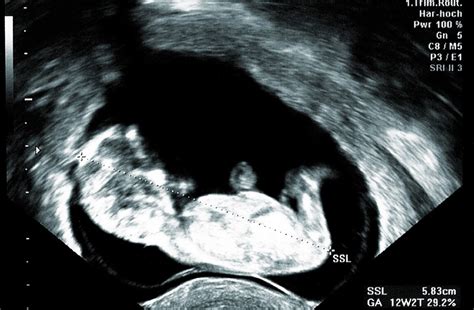

Vývoj dieťaťa: Vaše dieťa je teraz už plodom a rýchlo rastie. Na konci mesiaca je dlhé asi 6 až 7,5 cm a váži okolo 15 gramov, čo je približne veľkosť jablka. Hlava plodu už nie je neprimerane veľká vzhľadom k telu, tvorí asi polovicu jeho dĺžky. Na pokožke hlavy je rozpoznateľný základ vlasovej špirály. Oči sú menej vzdialené a uši sa presúvajú na boky hlavy, čo dodáva plodu ľudskejší výzor. Na prstoch rúk a nôh sú mäkké nechty a ruky začínajú byť viac funkčné. V ústach plodu sa vyvíjajú chuťové poháriky, sací reflex a formujú sa zárodky mliečnych zubov. Dieťa už tvorí moč a vylučuje ho do plodovej vody. Vonkajšie pohlavné orgány sú už dosť vyvinuté na to, aby sa mohlo určiť pohlavie dieťaťa. Srdcové ozvy plodu sú počuteľné pomocou Dopplerovho prístroja.

- 12. týždeň tehotenstva: Plod už má skutočnú podobu dieťatka.

- 13. týždeň tehotenstva: Záver prvého trimestra, dôležité je myslieť na zdravú stravu. V tomto období sa často vykonáva prvotrimestrálny screening.